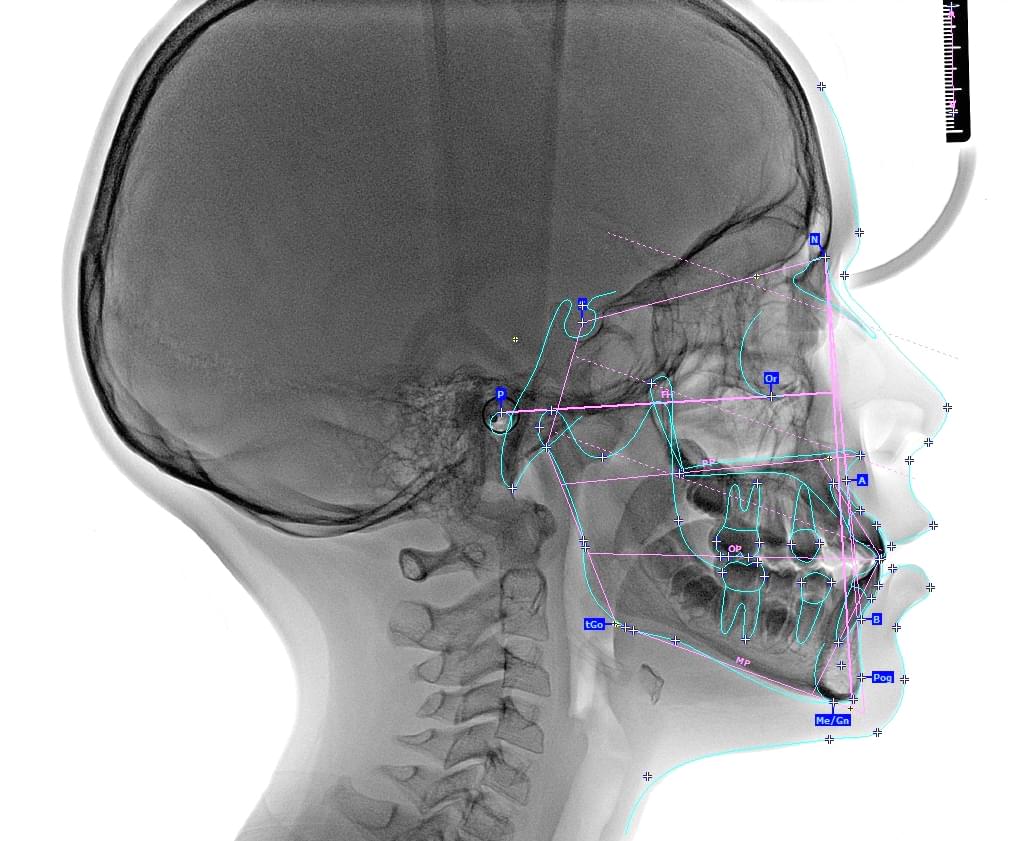

Výpočetní tomografie

(3d čelisťové snímky a snímky ústní dutiny)

CBCT Maxilofaciální diagnostika

Využíváme nejmodernější zařízení